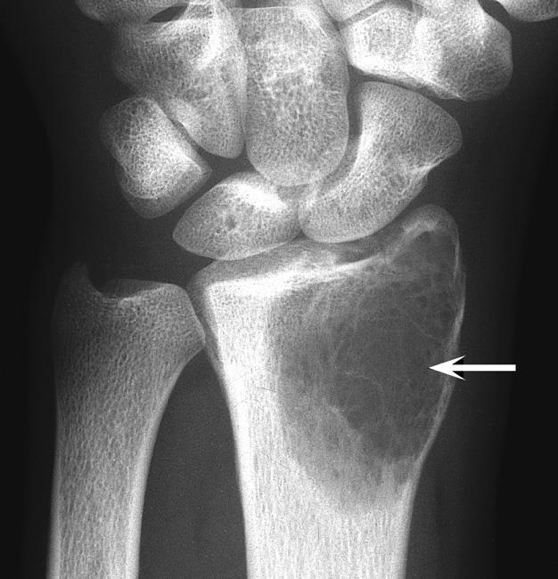

Definition

A bone tumour composed of osteoclast-type giant cells, may behave aggressively.

Clinical Features

- Pain, swelling, and restricted movement (especially near joints)

- Risk of pathological fracture